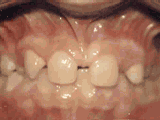

This patient's lateral incisors were congenitally missing. She had braces for twenty months to move the teeth into the correct position, then the missing teeth were replaced with bonded "Maryland" bridges.